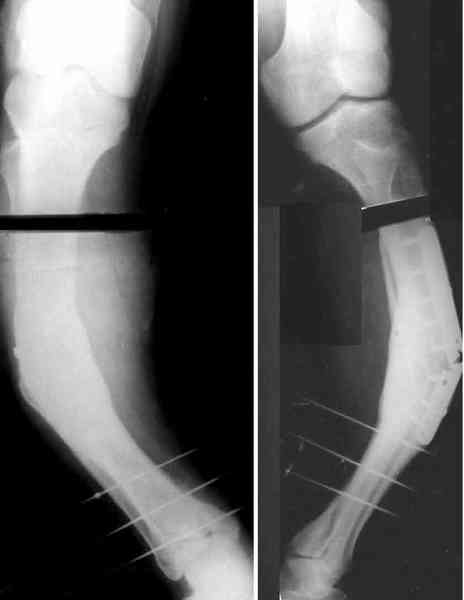

Удалили пластинку из двух доступов, винтик и спицу оставили. Сделан закрытый интрамедуллярный остеосинтез без рассверливания, прошло без

особенностей, стержень взял покороче, чтобы только до винта дошел. Снимок в приложении.

Кликните для загрузки файла 2k20309a.jpg

19KB (19793 bytes)

AC> Удалили пластинку из двух доступов, винтик и спицу оставили. Сделан

AC> закрытый интрамедуллярный остеосинтез без рассверливания, прошло без

AC> особенностей, стержень взял покороче, чтобы только до винта дошел.

AC> Снимок в приложении.

Хорошо получилось. Стержень только кажется тонковатым.

a> Хорошо получилось. Стержень только кажется тонковатым.

Спасибо. Стержень действительно всего 10 мм, но из-за винтов выше и ниже ничего никуда не денется. Тут и 11 (это максимальный диаметр

имеющихся у нас UFN) не заполнил бы канал, для этого надо было бы стержень 14-15 мм. В таком стержне можно и блокирующие винты разместить не 5 мм, а потолще, тогда можно было бы полную нагрузку разрешать сразу. Но у нас такого диаметра есть только старые 4-гранные, штыковидные. В принципе, можно и в них дырок наделать, мы штук 15 таких ввели, но 11-12 мм, и только 2 - 13 мм. Поскольку разверток гибких пока нет.